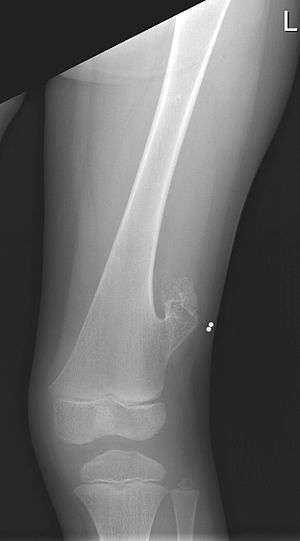

| X-ray of the left femur of a 10-year-old boy with an exostosis at the lateral side, just above the knee. | |